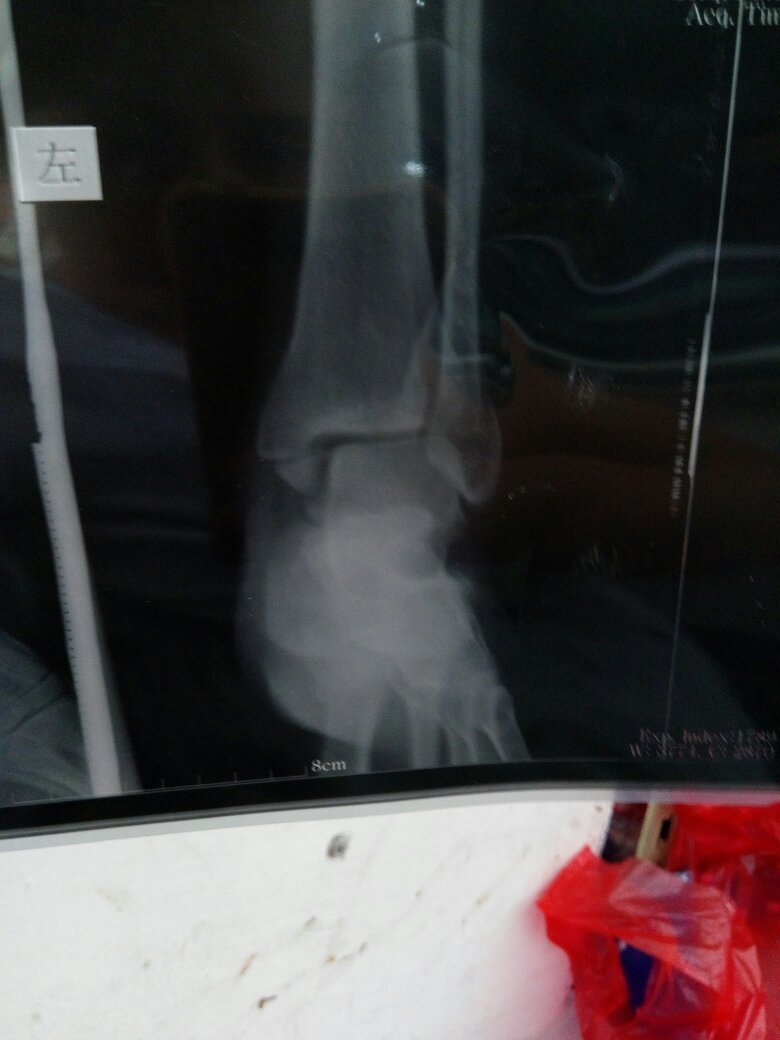

怀孕七个月了,左脚踝两边骨折,到生孩子时候能慢慢走路吗?后面有片子帮我看看吧 谢谢 点击展开 133*****340_heC3 2016-09-23 10:10 满意回答 您好,根据描述,考虑可以寸细评石膏外固定。怀孕期间,尽量不做。拍径劣片概豆放射检查 cn#afBBaVapka 2016-09-23 10:14 宝宝知道提示您:回答为网友贡献,仅供参考。 相关问题 那要是脚踝怀疑骨折,是拍什么片子呢 你好,我在排卵期陪我儿子拍脚踝骨折片子,现在怀孕42天了 脚趾骨折57天了,脚踝还是肿,现在可以下地走路了吗?同房影响恢复吗?拿热水泡脚有好处吗?谢谢